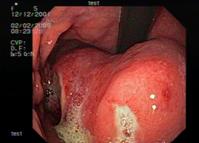

Полипы и опухолеподобные поражения желудка. Результатом уточняющей диагностики 68 больных V группы с визуальной картиной различных полиповидных образований стало выявление среди них в 10,3% наблюдений эндосонографических признаков рака желудка (рис. 6), причем в 8,8% диагностирован ранний рак и в 1,5% распространенный. Различия полученных результатов статистически достоверны (p<0,001). Качественная ультразвуковая недооценка раннего рака желудка произошла в 2,9% случаев среди пациентов с очаговой гиперплазией и полипом.

Рис. 6. 65 лет. Гистология – высокодифференцированная аденокарцинома:

а - визуальная картина полипа желудка, подозрительного в отношении малигнизации;

б – на эндосонограмме - гипоэхогенное образование, исходящее из слизистой оболочки,

с инвазией в мышечный слой. Эхографические признаки рака желудка.